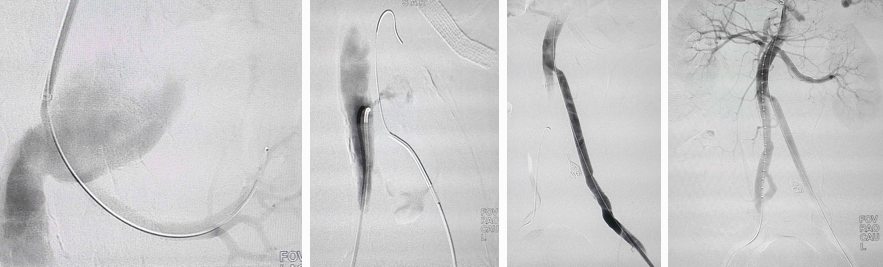

远端破口创新治疗技术

★ WeFlow-EndoPatch腔内补片系统

1.手术步骤:

2. 临床试验(N=27)

安全性:术后30天主要不良事件(MAE)发生率仅3.7%(1例因新冠肺炎呼吸衰竭)

有效性(术后6个月,n=15):

15例患者完成术后6个月CTA影像学随访。15例患者术前胸主动脉假腔最大直径 33.61±26.95 mm,术后6个月胸主动脉假腔最大直径缩小为 28.92±24.22 mm;术前腹主动脉假腔最大直径 25.96±7.27 mm,术后6个月腹主动脉假腔最大直径缩小为 22.07±5.69 mm。

*15例患者共植入29枚补片

15例患者术后6个月胸降主动脉段及腹主动脉段假腔均实现血栓化。